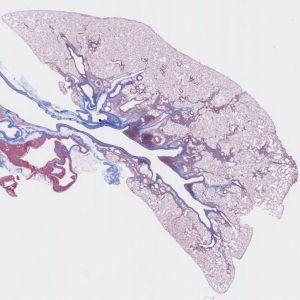

Rat lung stained with Masson’s trichrome stain.

Pulmonary fibrosis is the formation or development of excess fibrous connective tissue (fibrosis) in the lungs. Pulmonary fibrosis is a gradual exchange of normal lung parenchyma with fibrotic tissue, causing irreversible decrease in oxygen diffusion capacity. In addition, decreased compliance makes pulmonary fibrosis a restrictive lung disease. It is the main cause of restrictive lung disease that is intrinsic to the lung parenchyma. With Masson’s trichrome, the collagen in a rat lung section is stained blue and therefore very easy to distinguish from other tissue types. A magnification of 5X and a random 50% sampling is sufficient for an accurate and robust estimation of the collagen to tissue ratio.